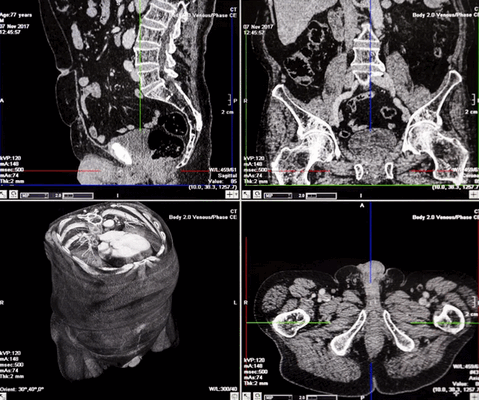

Органы малого таза. Компьютерное сканирование назначают при подозрении на заболевания репродуктивной системы мужчин и женщин. КТ внутренних органов малого таза показывает:

аденому, простатит, камнеобразование, рак;

очаговое поражение мочевого пузыря (сканирование проводят для оценки инвазии опухоли в окружающие ткани), камни, цистит;

парапроктит, проктит, аппендицит, инородное тело в прямой кишке;

эндометрит, спаечные процессы, сальпингоофорит, кисты яичников, опухолевые патологии внутренней оболочки матки, шейки, врожденные пороки развития и пр.